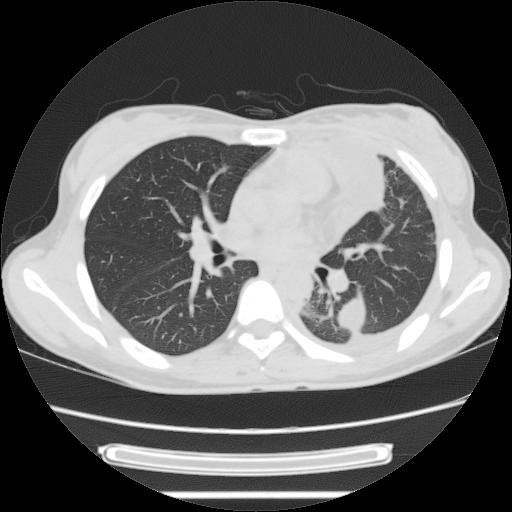

女,29岁,胸部不适,在外院胸片提示胸腔积液,到我院ct检查。

肺窗:

1、左侧包裹性积液伴叶间积液 2、右肺多发结节考虑增殖结节

左肺上叶不张,左侧胸水,叶间裂积液,纵隔淋巴结,脾脏钙化,考虑左肺上叶支气管内膜结核,结核性胸膜炎,脾结核

右肺多发结节。左胸腔多发包裹性积液。